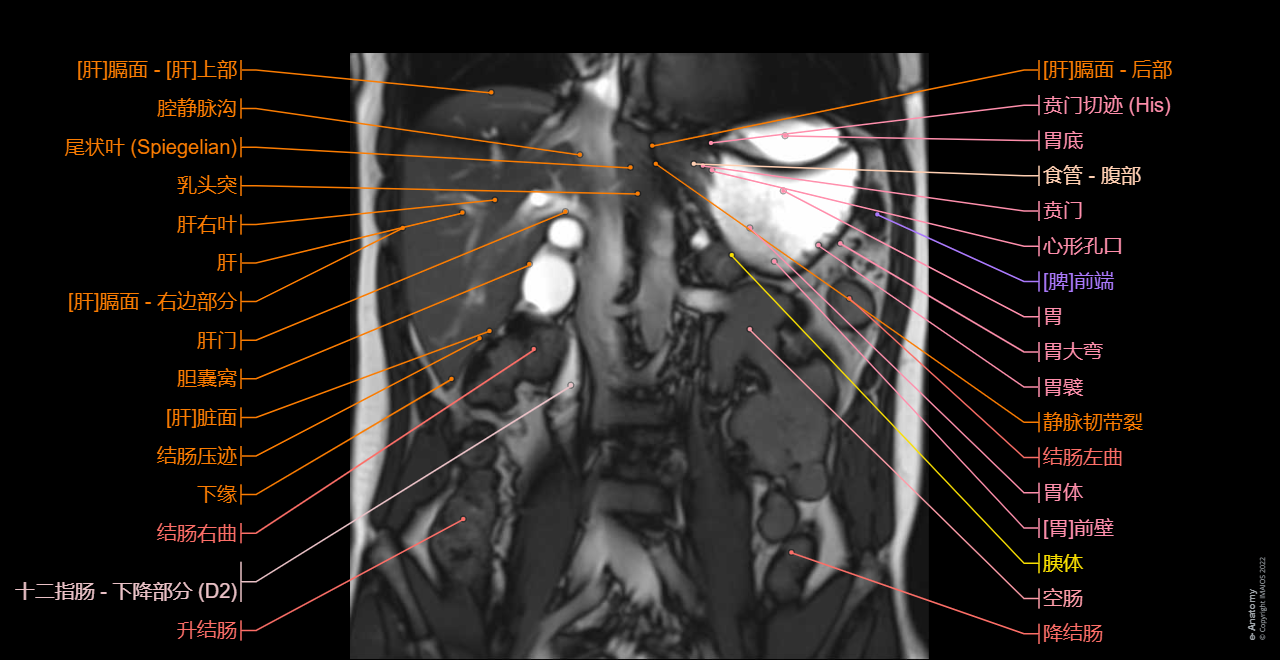

Coronal true FISP: This sequence is the first of our MRCP protocol, on the upper abdomen to establish the location of the extrahepatic bile ducts. But in this module of e-Anatomy, put it at the end because of its lack of relevant medical information on the biliary tract.